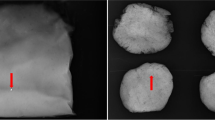

2.3.1 Fragment number, volumes and XYZ-positions from CT datasets

The CT image sequences were saved in DICOM format and processed using the open source software Horos [28]. Reconstruction voxel size was 0.212 × 0.212 × 0.25 or 0.212 × 0.212 × 0.5 mm. Using 3D Volume Viewer, window level and window width were adjusted to remove most soft tissues and bones while retaining the metal fragments. Each image sequence was exported as TIFF files. Remaining bone structures and structures resulting from bright radiation of fragments were removed by setting a threshold and editing using the open source software FIJI [29]. The 3D Object Analyzer tool was applied to calculate fragment properties such as numbers, volumes, and XYZ-coordinates. Volumes were not adjusted for overestimation by blooming artifacts [30]. Handling of roe deer and tissues for CT scans and meat processing steps may have caused some dislocation of fragments from their original location, separation of clustered fragments or clustering of fragments, leading to some variability in fragment numbers and sizes.